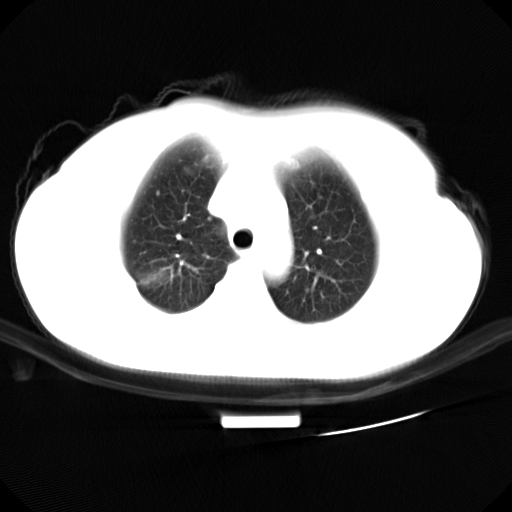

以下是引用zjzjr在2007-3-23 13:28:00的发言:[br]右肺上叶后段可见一结节状高密度影,可见毛刺征,胸膜凹陷征及血管导入征,纵隔内可见肿大淋巴结影.考虑右肺上叶周围型肺癌伴纵隔淋巴结转移.

以下是引用zjzjr在2007-3-23 13:28:00的发言:[br]右肺上叶后段可见一结节状高密度影,可见毛刺征,胸膜凹陷征及血管导入征,气管前腔静脉后可见肿大淋巴结影.考虑右肺上叶周围型肺癌伴纵隔淋巴结转移.